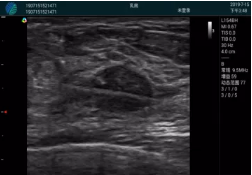

清晰顯示腺體內(nèi)低回聲快影,邊界清晰,包膜較光滑

確定進(jìn)針路徑并實(shí)時(shí)監(jiān)測(cè)抽吸針與腫塊位置關(guān)系

抽吸針進(jìn)入腫塊內(nèi)部進(jìn)行旋切

抽吸過(guò)程中可見(jiàn)腫塊明顯縮小,并根據(jù)腫塊位置改變針道位置

抽吸旋切后再進(jìn)行超聲復(fù)查,原腫塊區(qū)域未見(jiàn)殘留組織及出血